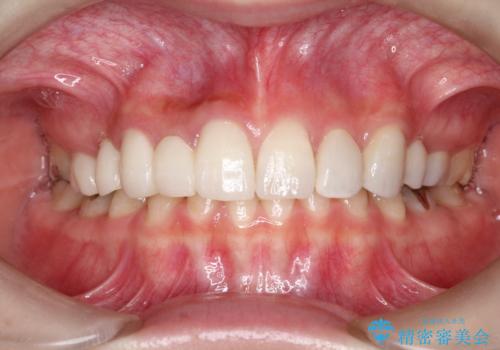

オールセラミックによるやりかえを行いました。

色調もまわりの歯に合わせて、形態も患者様のご希望に沿うように製作させていただきました。